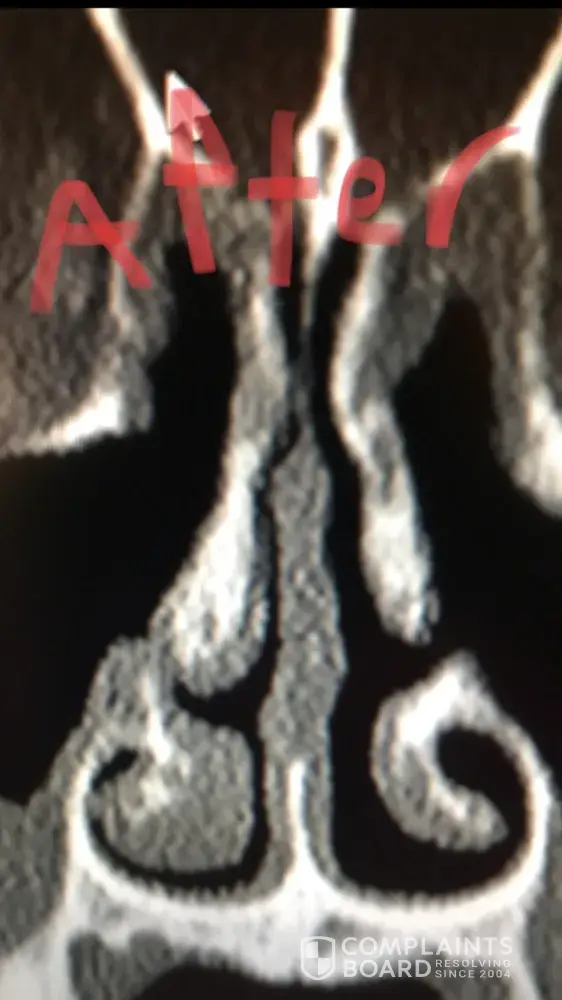

For people reading this, I have included x-ray images of the inside of my nose, before and after my surgery with him. As you can see from these images, my nasal airway was equally open on both sides, before surgery, and the septoplasty didn't need to be done. By performing it, he severely narrowed the right side of my nasal airway.

He performed this unnecessary surgery to collect that additional insurance money. There is no other explanation for this. Furthermore, when I later contacted him, and told him that my breathing was worse, and I suspected it was a problem with my septum, he told me that he wouldn't be able to perform the revision septoplasty (make the septum way it was before). Therefore, not only is he greedy, by performing unnecessary surgeries, but he is incompetent, for not being able to fix his mistakes.

Dr Raviv performed two surgeries on me: endoscopic sinus surgery (where they widen the sinus passages), and septoplasty (where they straighten the septum). The septoplasty, however was completely unnecessary, and severely narrowed the right side of my nasal airway. For people reading this, I have included x-ray images of my sinuses, before and after my surgery with Dr. Raviv. As you can see from the surgery, my airway was much more open, and equal on both sides, before my surgery with him.